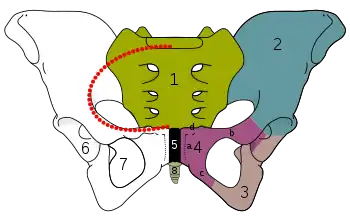

| Pubis (bone) | |

Pelvic girdle | |

Male pelvis with pubis at bottom | |

The sacrum and pelvic bone, with parts labelled. The pubic bone consists of the body and superior pubic ramus (4), and the inferior pubic ramus (3), which join at the pubic symphysis. The gap between them is the obturator foramen.

The sacrum and pelvic bone, with parts labelled. The pubic bone consists of the body and superior pubic ramus (4), and the inferior pubic ramus (3), which join at the pubic symphysis. The gap between them is the obturator foramen. Right hip bone. External surface.